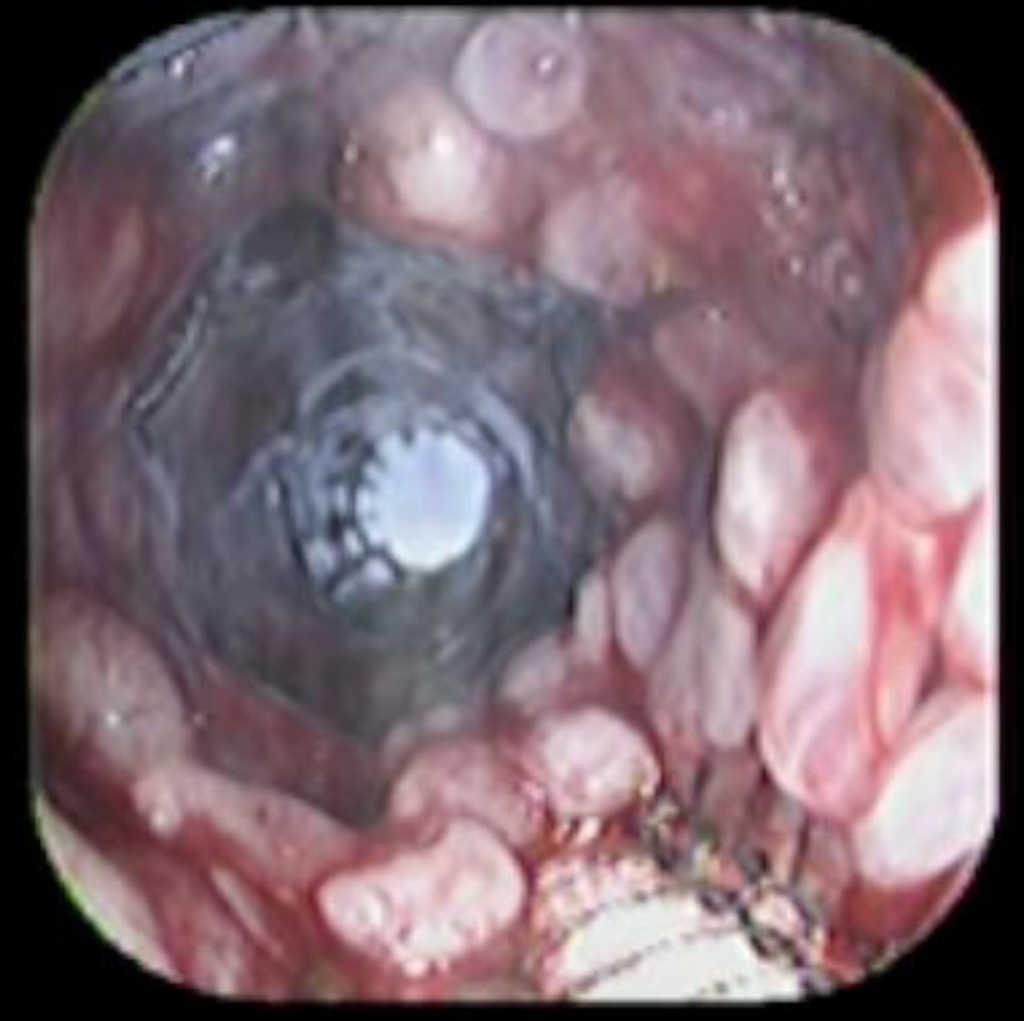

Case reportA 41-year-old man underwent elective laparoscopic Heller myotomy for achalasia; during the procedure a perforation of the esophageal wall was observed, and primary closure of the defect was attempted. The patient started with PO on day three, but he complained of chest pain and fever. Immediately CT scan with oral contrast was performed. A free leakage at esophago-gastric junction was observed. A 15 cm PSEMS (Ultraflex esophageal NG covered (120 mm) stent, Boston Scientific, Natick, MA) was placed across the defect, leading to the distal 1.5 cm non cover into the stomach and the proximal 1.5 cm non cover at 30 cm from incisor (Figure 1). A control CT scan with oral contrast showed good position of the stent, without evidence of leakage. The patient's clinical status improved and began to swallow normally, but showed numerous episodes of reflux despite PPI use. We leave the PSEMS for 26 days beside the reflux symptoms. During the endoscopic procedure to remove the stent the presence of tissue embedding along the covered portion of the PSEMS was noted (Figure 2). The stent was pulled out with an alligator forceps with out major complications and the cover of the PSEMS was seen to be totally destroyed (Figure 3).

Figure 1. The image shows the stent application.